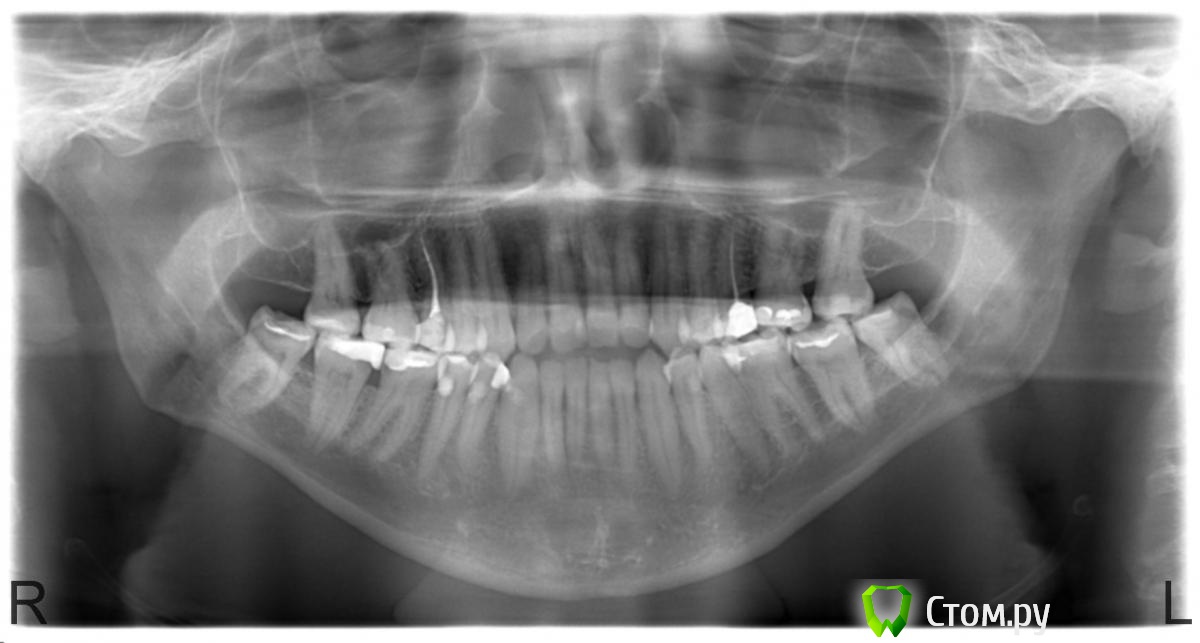

Ashmangos Опубликовано 15 октября, 2014 Поделиться Опубликовано 15 октября, 2014 Здравствуйте!Не давно сделали рентген всей ротовой полости и обнаружили у меня кисту рядом с зубом, где был удален нерв - Правый верхний, где-то после "клыков" , если можно их так назвать.До этого на этот зуб мне делали световую пломбу, если я не ошибаюсь (было 2-3 года назад - точно не помню уже).Посоветуйте, что делать с этим?Фото в приложении. Заранее спасибо! С уважением, Николай. Муром. Ссылка на комментарий

red_butler Опубликовано 15 октября, 2014 Поделиться Опубликовано 15 октября, 2014 Найдите хорошего эндодонтиста, и лечите зуб 3 Ссылка на комментарий